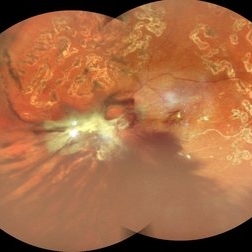

TRACTIONAL RETINAL DETACHMENT IN A CASE OF VASCULITIS

MONTAGE OF A 27 YEAR OLD MALE WITH TREACTIONAL RETINAL DETACHMENT IN A CASE OF VASCULITIS

Photographer: Dr. Akansha Sharma-Retina Foundation, Ahmedabad

Condition/keywords: pan-retinal photocoagulation (PRP), tractional retinal detachment, VASCULITIS